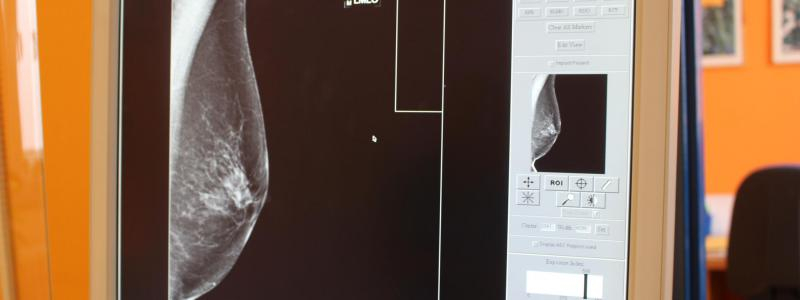

Na screening jednou za dva roky Neméně důležitou součástí prevence je i mamografický screening, který je zdarma pro všechny ženy od 45 let. „Každé dva roky by žena měla jít na mamární screening na některé ze screeningových pracovišť,“ upozorňuje lékařka. Nemocnice Pardubického kraje má screeningové pracoviště ve Svitavách a spolupracuje také s řadou ambulantních screeningových pracovišť s přímou vazbou na Pardubickou nemocnici. Kromě toho je Nemocnice Pardubického kraje jedním ze dvou subjektů, které tvoří Komplexní onkologické centrum Pardubického kraje, jedno ze 14 vysoce specializovaných pracovišť v České republice.